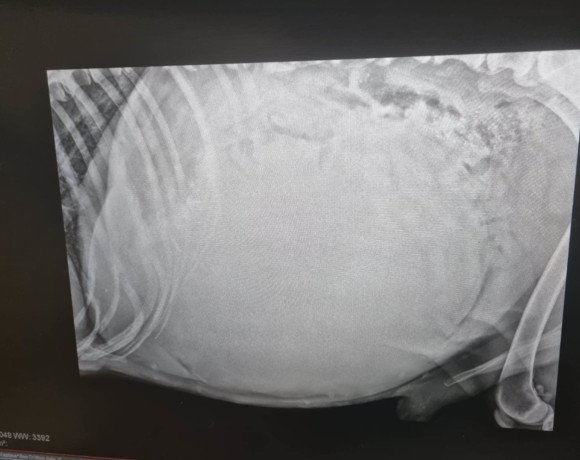

Die Untersuchungen beim Tierarzt haben leider ergeben, dass er einen Milztumor hat und der Krebs bei Dedo bereits so weit fortgeschritten ist, dass eine Operation keinen Sinn mehr ergeben würde. Die Narkose wäre für ihn ein zu großes Risiko, und wir wollen ihm unnötiges Leiden ersparen. Stattdessen haben wir beschlossen, Dedo seine letzten Tage, Wochen oder Monate so angenehm wie möglich zu gestalten. Dedo darf nun bei unserer Tierschützerin vor Ort im Zwinger leben, da er das Leben draußen gewohnt ist und drinnen nicht bleiben möchte. Sie sorgt liebevoll für ihn und kocht ihm sogar seine Mahlzeiten selbst – eine kleine Freude, die ihm in dieser schweren Zeit geblieben ist. Bitte helft uns, Dedo die letzten Momente seines Lebens so schön wie möglich zu machen. Eine Futter- oder Medizinpatenschaft würde uns sehr helfen, damit wir Dedo in seiner letzten Zeit angemessen versorgen können.